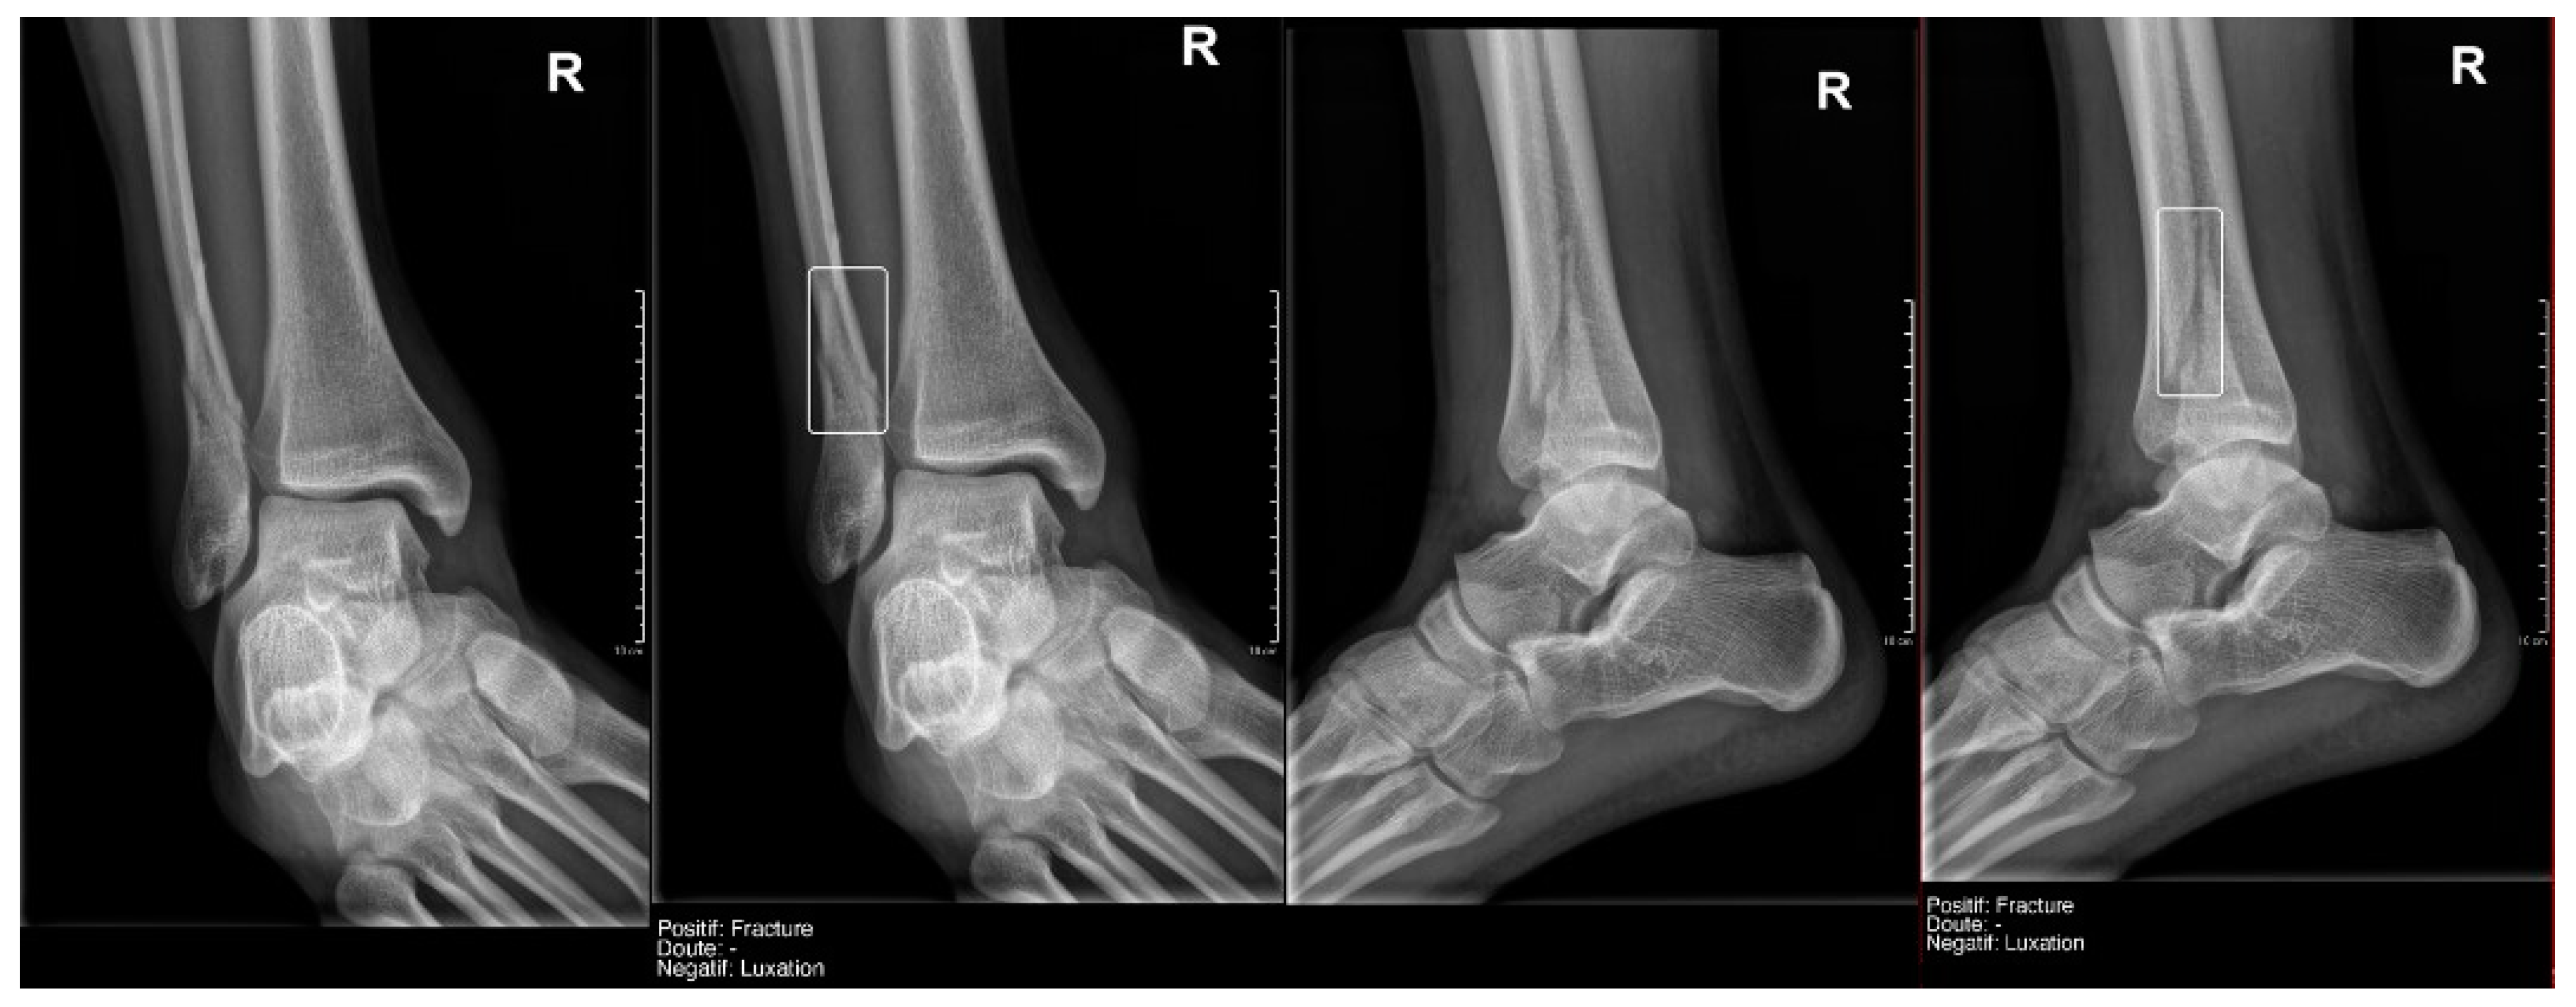

Regarding fracture detection (Table 3), a particularly notable finding was that the readings by Milvue and the resident show generally very high values for Sens, Spec, PPV, NPV, and AUC, with data similar to those described in the literature. (Figure 5 and Figure 6).

Figure 5.

True positive fracture of the distal fibula correctly recorded by AI and radiology resident.